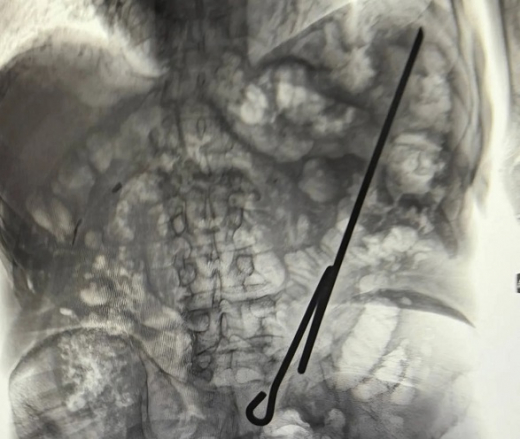

За одну ночь врачи городской больницы №3 нашли в своих пациентах самодельный инструмент и паразита. Как сообщил минздрав в паблике во ВКонтакте, дежурство в конце января запомнилось им особенно. 84-летний мужчина упал и напоролся на самодельный инструмент, которым и проводил работы. После этого пенсионера доставили в больницу, где врачи сделали все необходимые исследования. Пожилому мужчине потребовалась операция: извлекать инструмент пришлось хирургическим путём. К счастью, ни один орган брюшной полости не был задет. Сыграло роль и то, что пациент был голоден. По состоянию на 8 февраля пенсионера выписали. Второй пациент, 49-летний мужчина, попал в больницу с диагнозом «дирофиляриоз». Воронежца до этого лечили в инфекционной больнице. — Это редкое, но опасное паразитарное заболевание, вызываемое гельминтами (червь-паразит) рода Dirofilaria («злая нить»). Источником инфекции у людей служат домашние животные, преимущественно собаки, реже кошки. Промежуточным хозяином червей выступают комары, которые переносят инвазивные личинки. Роль в передачи личинок могут играть и другие кровососущие насекомые: блохи, слепни, вши, клещи. При этом пациент отмечал, что тесно общается со своими домашними животными, — рассказали в региональном минздраве. Мужчина жаловался на боли и перемещение узелка под кожей. После исследований медики извлекли из подкожной клетчатки гельминта, а пациента вернули в инфекционную больницу.